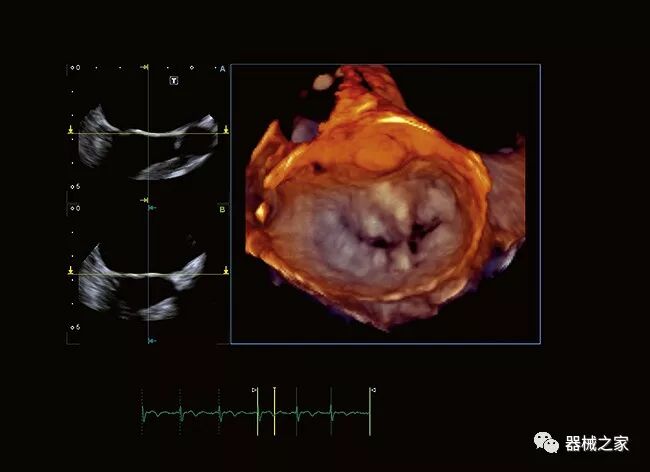

Vivid E95心脏成像系统

2018年,GE医疗集团发布了其cSound图像重建技术的Imaging Elevated版本。该技术有助于Vivid E95心脏成像系统的成像质量,工作流程和量化。它利用GPU处理来提高音量帧速率,GE称为音量最大值或Vmax。与上一代系统相比,这使得TEE的帧速率几乎可以达到三倍。

佳能Aplio 900 CV系统还在2018年推出了一种新方法,通过称为四腔室跟踪的回声可视化心脏。它在一个三维视图中跟踪所有四个腔室的血容量。它提供腔室的舒张末期和收缩末期视图。这允许一次完成整个心脏功能的图像,而不是一次查看一个腔室。